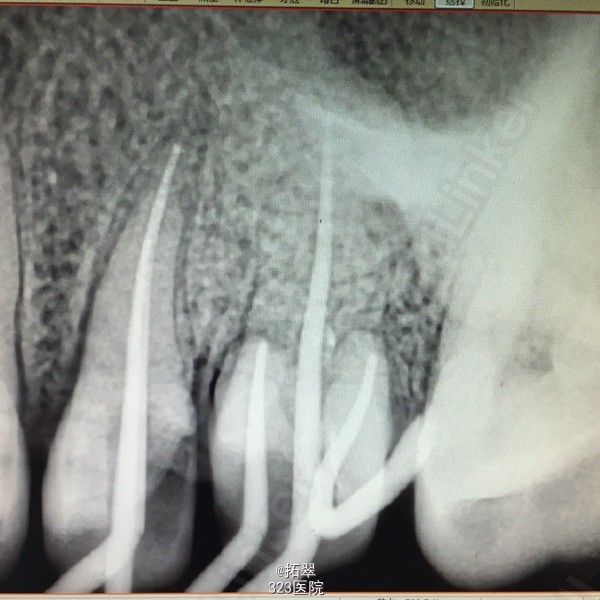

左上6金属冠,叩(+)冷(-),松(-) 左上5远中颌面缺损,冷(+),叩(-),松(-) X线检查:左上6髓腔内充填物,根尖少于阴影,根管内未见充填物。 左上5龋深及髓。

诊断:左上6尖周炎 左上5慢性牙髓炎 建议:左上6根管再治疗后+桩+冠修复 左上5RCT+桩+冠 处理:左上6拆冠,清理根管,MB、DB长16mm,扩至F1,P长17mm,扩至F1,双氧水反复冲洗,木馏油棉开放 左上5开髓,置乳失,丁香油棉安抚,ZOE暂封。